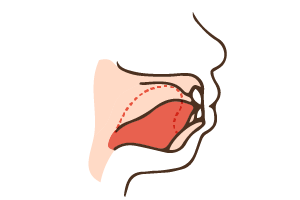

口で呼吸をすると舌の位置が下がり、上あごに力が伝わらず、上顎の成長が遅れます。また舌が上の前歯を押すと出っ歯になり、下の前歯を押すとと噛み合わせが正常と逆になります。鼻呼吸への改善が必要です。

口で呼吸をすると舌の位置が下がり、上あごに力が伝わらず、上顎の成長が遅れます。また舌が上の前歯を押すと出っ歯になり、下の前歯を押すとと噛み合わせが正常と逆になります。鼻呼吸への改善が必要です。